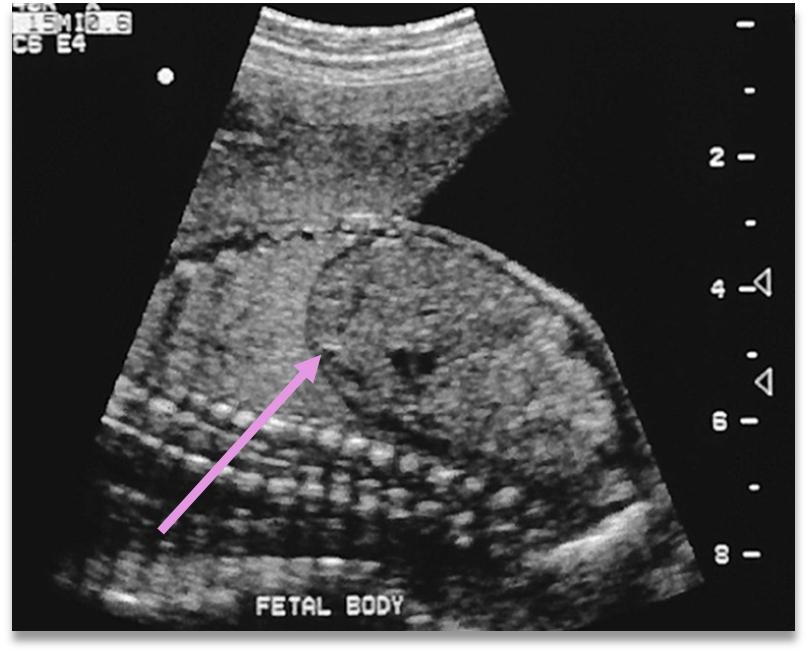

CDH